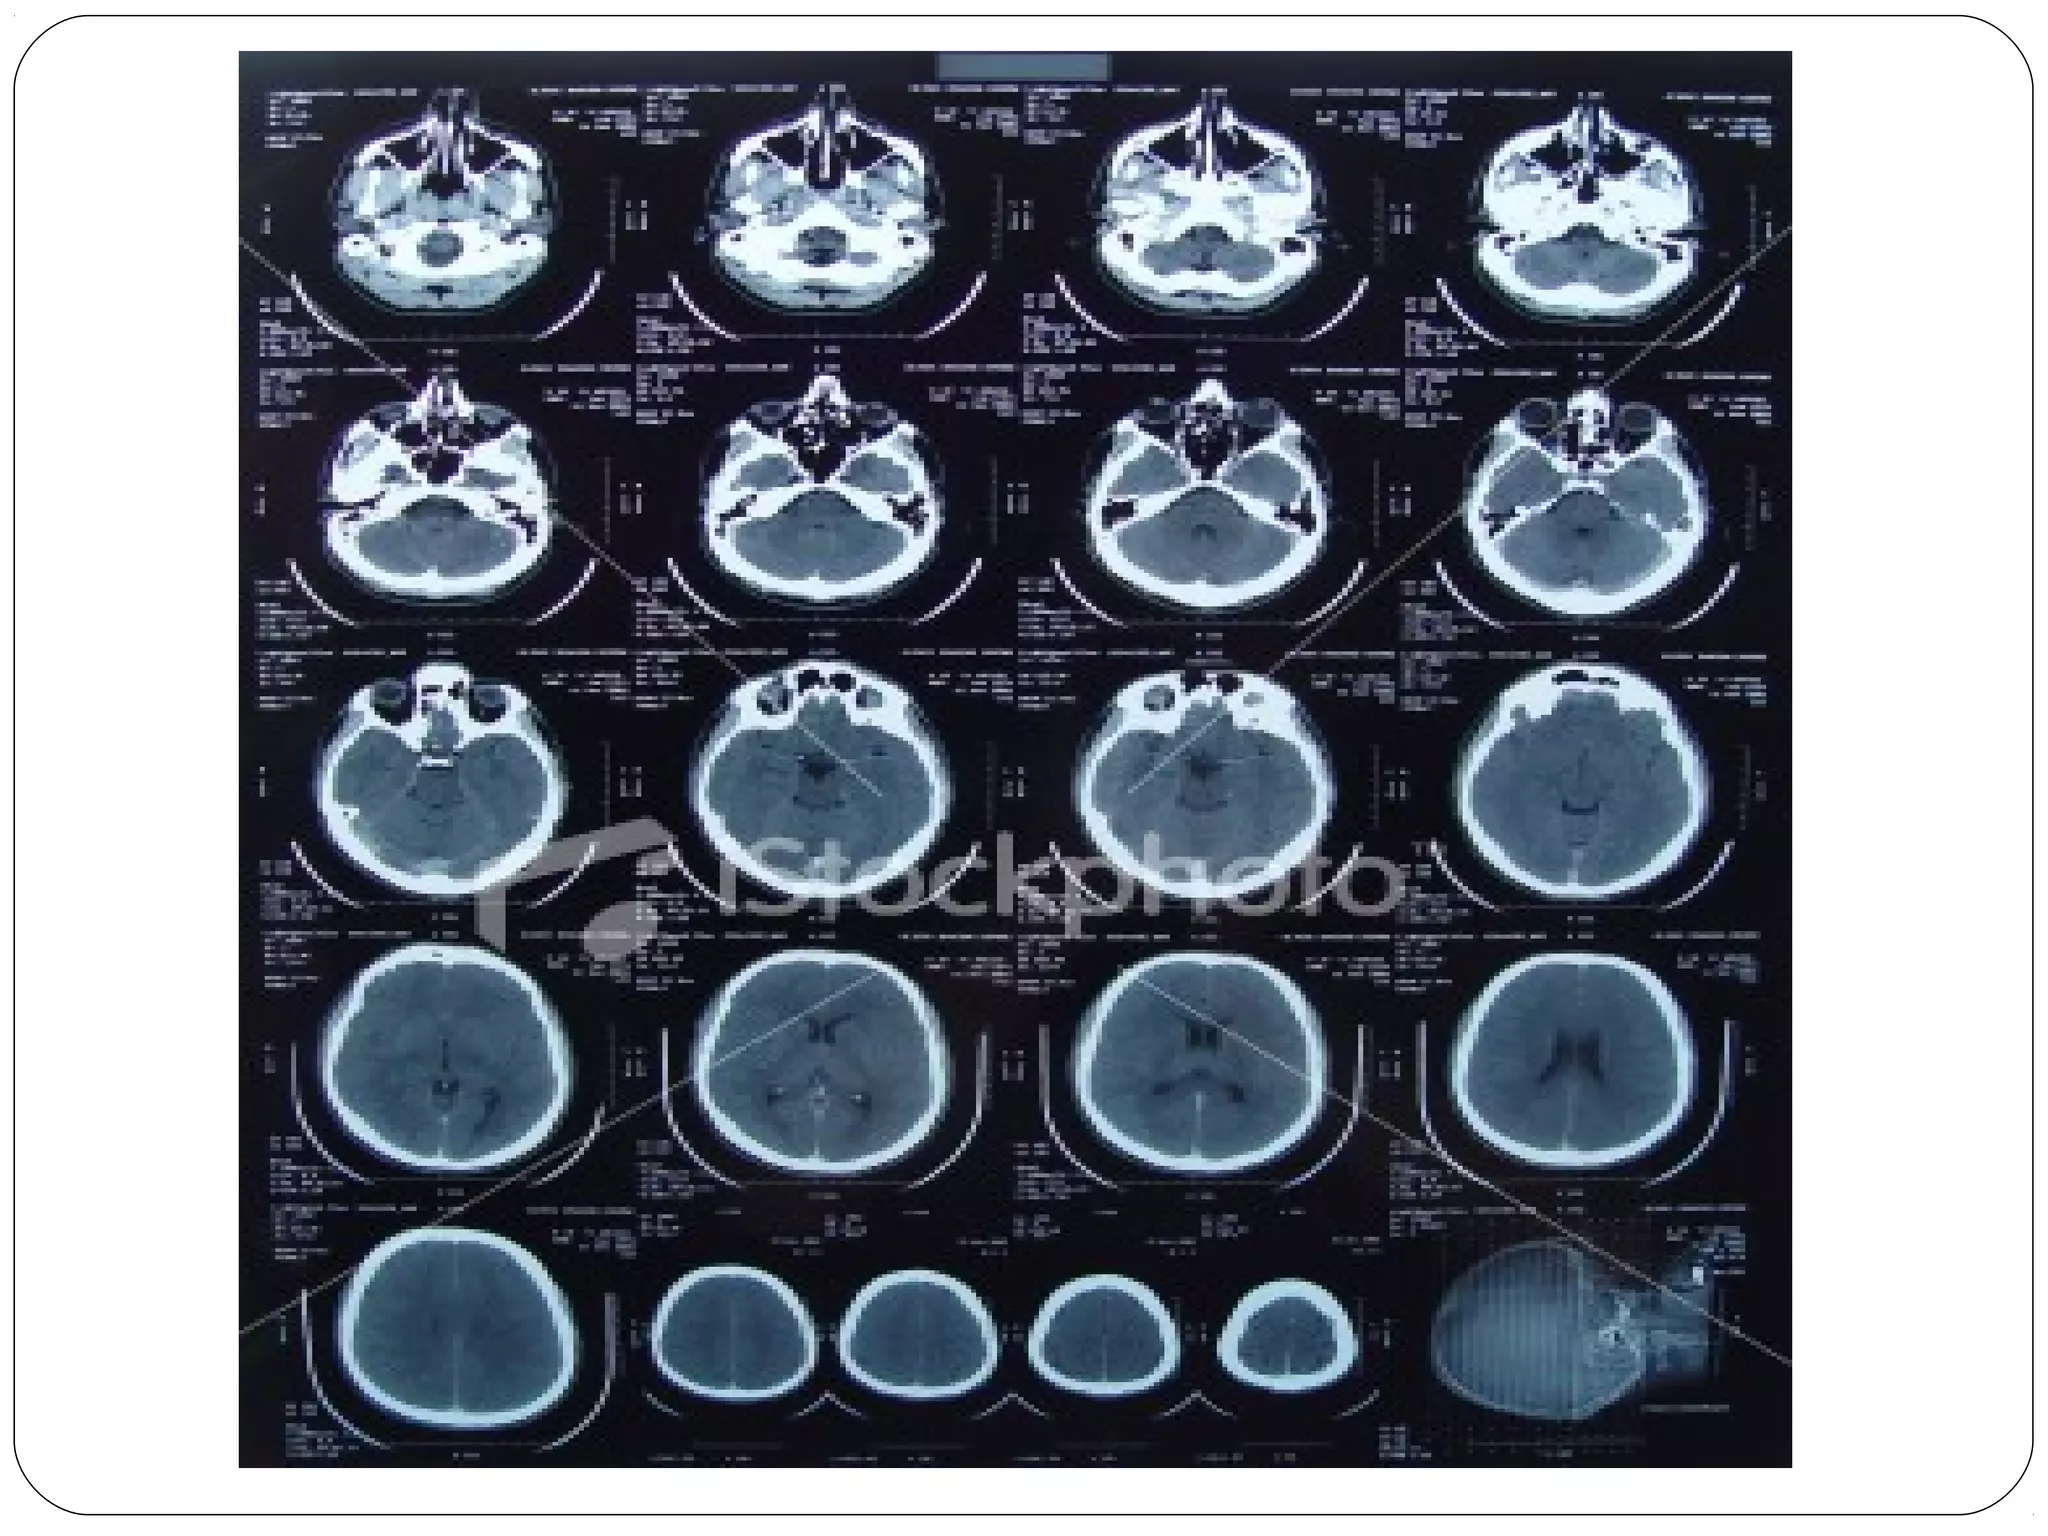

Magnetic Resonance Imaging (MRI) Whatis a MRI? • The use of a High Power Magnet (.3 -2.0Teslas)To align hydrogen atoms in the body to which a radio wave frequency is applied to produce an image HigherTesla level= increased resolution

• 57.

Magnetic Resonance Imaging 1.Also called “MRI” 2. Image formed by transmitting and receiving radio waves inside a high magnetic field 3. Image “slices” reconstructed by computation 4. The image formed is related to: 1. Scanner settings 2. Patient hydrogen density 3. Patient hydrogen chemical/physical environment 5. Image display on computer or multiple films